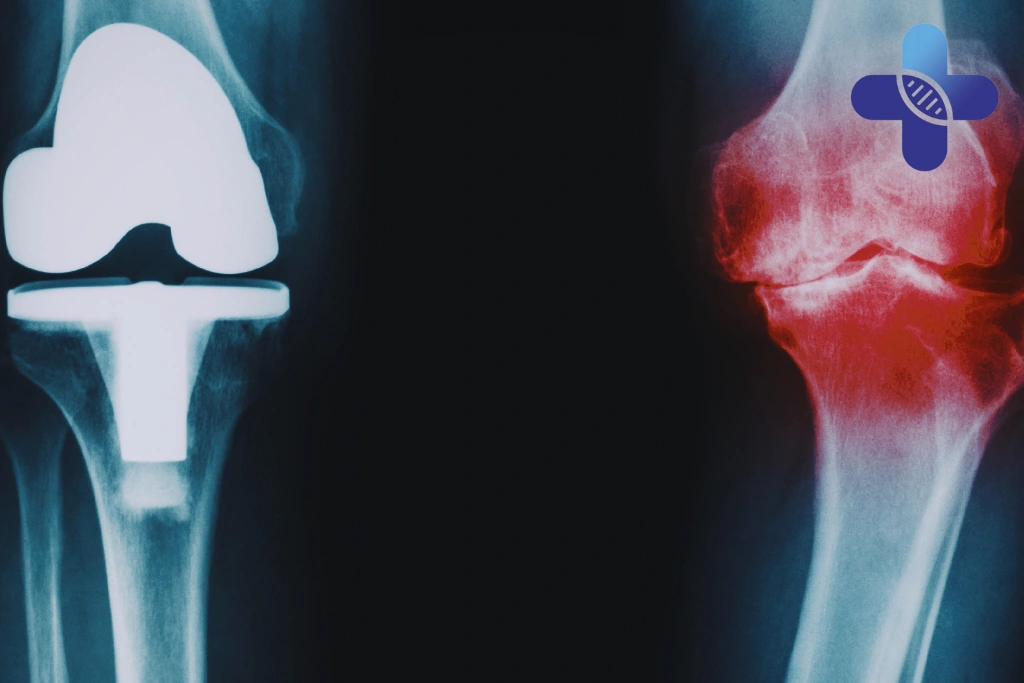

Each of these conditions affects the knee differently. For example, osteoarthritis knee treatment strategies may differ from approaches used for soft tissue strain. A structured evaluation helps determine whether pain is primarily inflammatory, mechanical, or degenerative in nature.

Regenerative Approaches for Knee Pain

In recent years, regenerative medicine Bali has gained attention as part of advanced knee pain treatment Bali strategies.

Regenerative approaches focus on supporting the body’s own repair mechanisms rather than only suppressing symptoms. These may include cell-based therapies evaluated under structured medical supervision.

At a Medical Clinic Bali offering regenerative evaluation, eligibility for stem cell therapy is typically determined through comprehensive assessment rather than symptom severity alone. Factors such as degree of degeneration, stability of the joint, and overall health are considered.

It is important to understand that regenerative approaches do not guarantee cartilage restoration and are not suitable for every case. Patient selection remains essential, which is why reviewing criteria such as Who Is a Good Candidate is often recommended before considering advanced therapies.